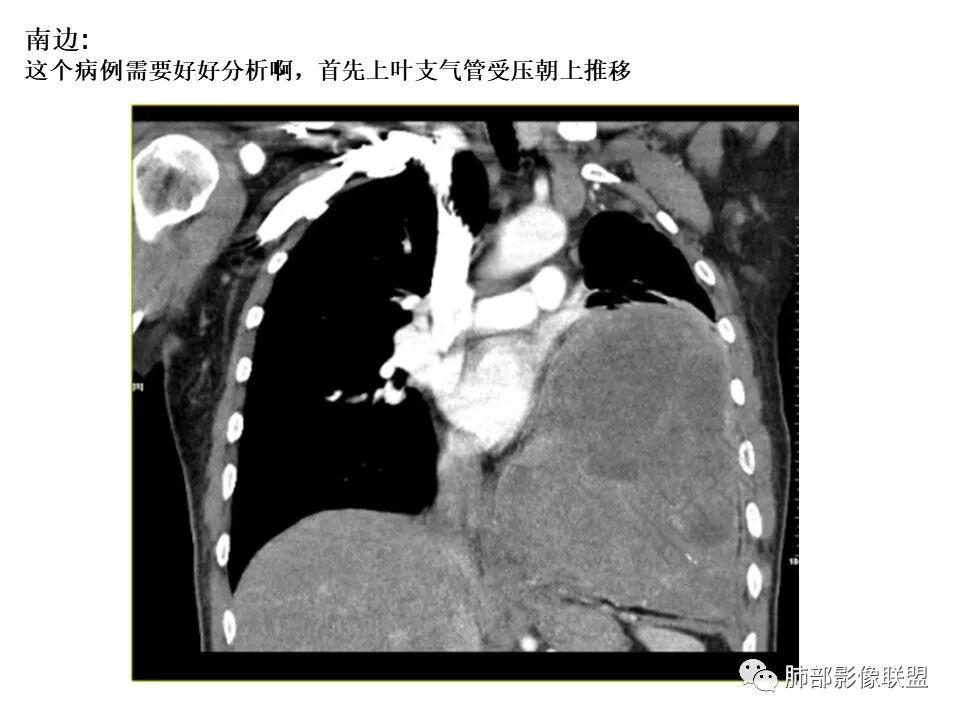

南边:

还是支持脏层胸膜来源SFT首选,其次肺内肉瘤

因为:

1局部胸膜起源,所以与胸膜分界不清

2、肺内病变,局部胸膜侵犯

如果胸膜侵犯,局限在这里,而且支气管侵犯不是很明显,似乎不合理

内部坏死都可以,钙化,SFT几率高一些

2.左肺巨大块影,上部边界较清楚,占据胸腔大部,对于左肺,“占据”及“推移”兼而有之,左肺上叶支气管推移狭窄,下叶支气管截断。下肺动脉穿行!